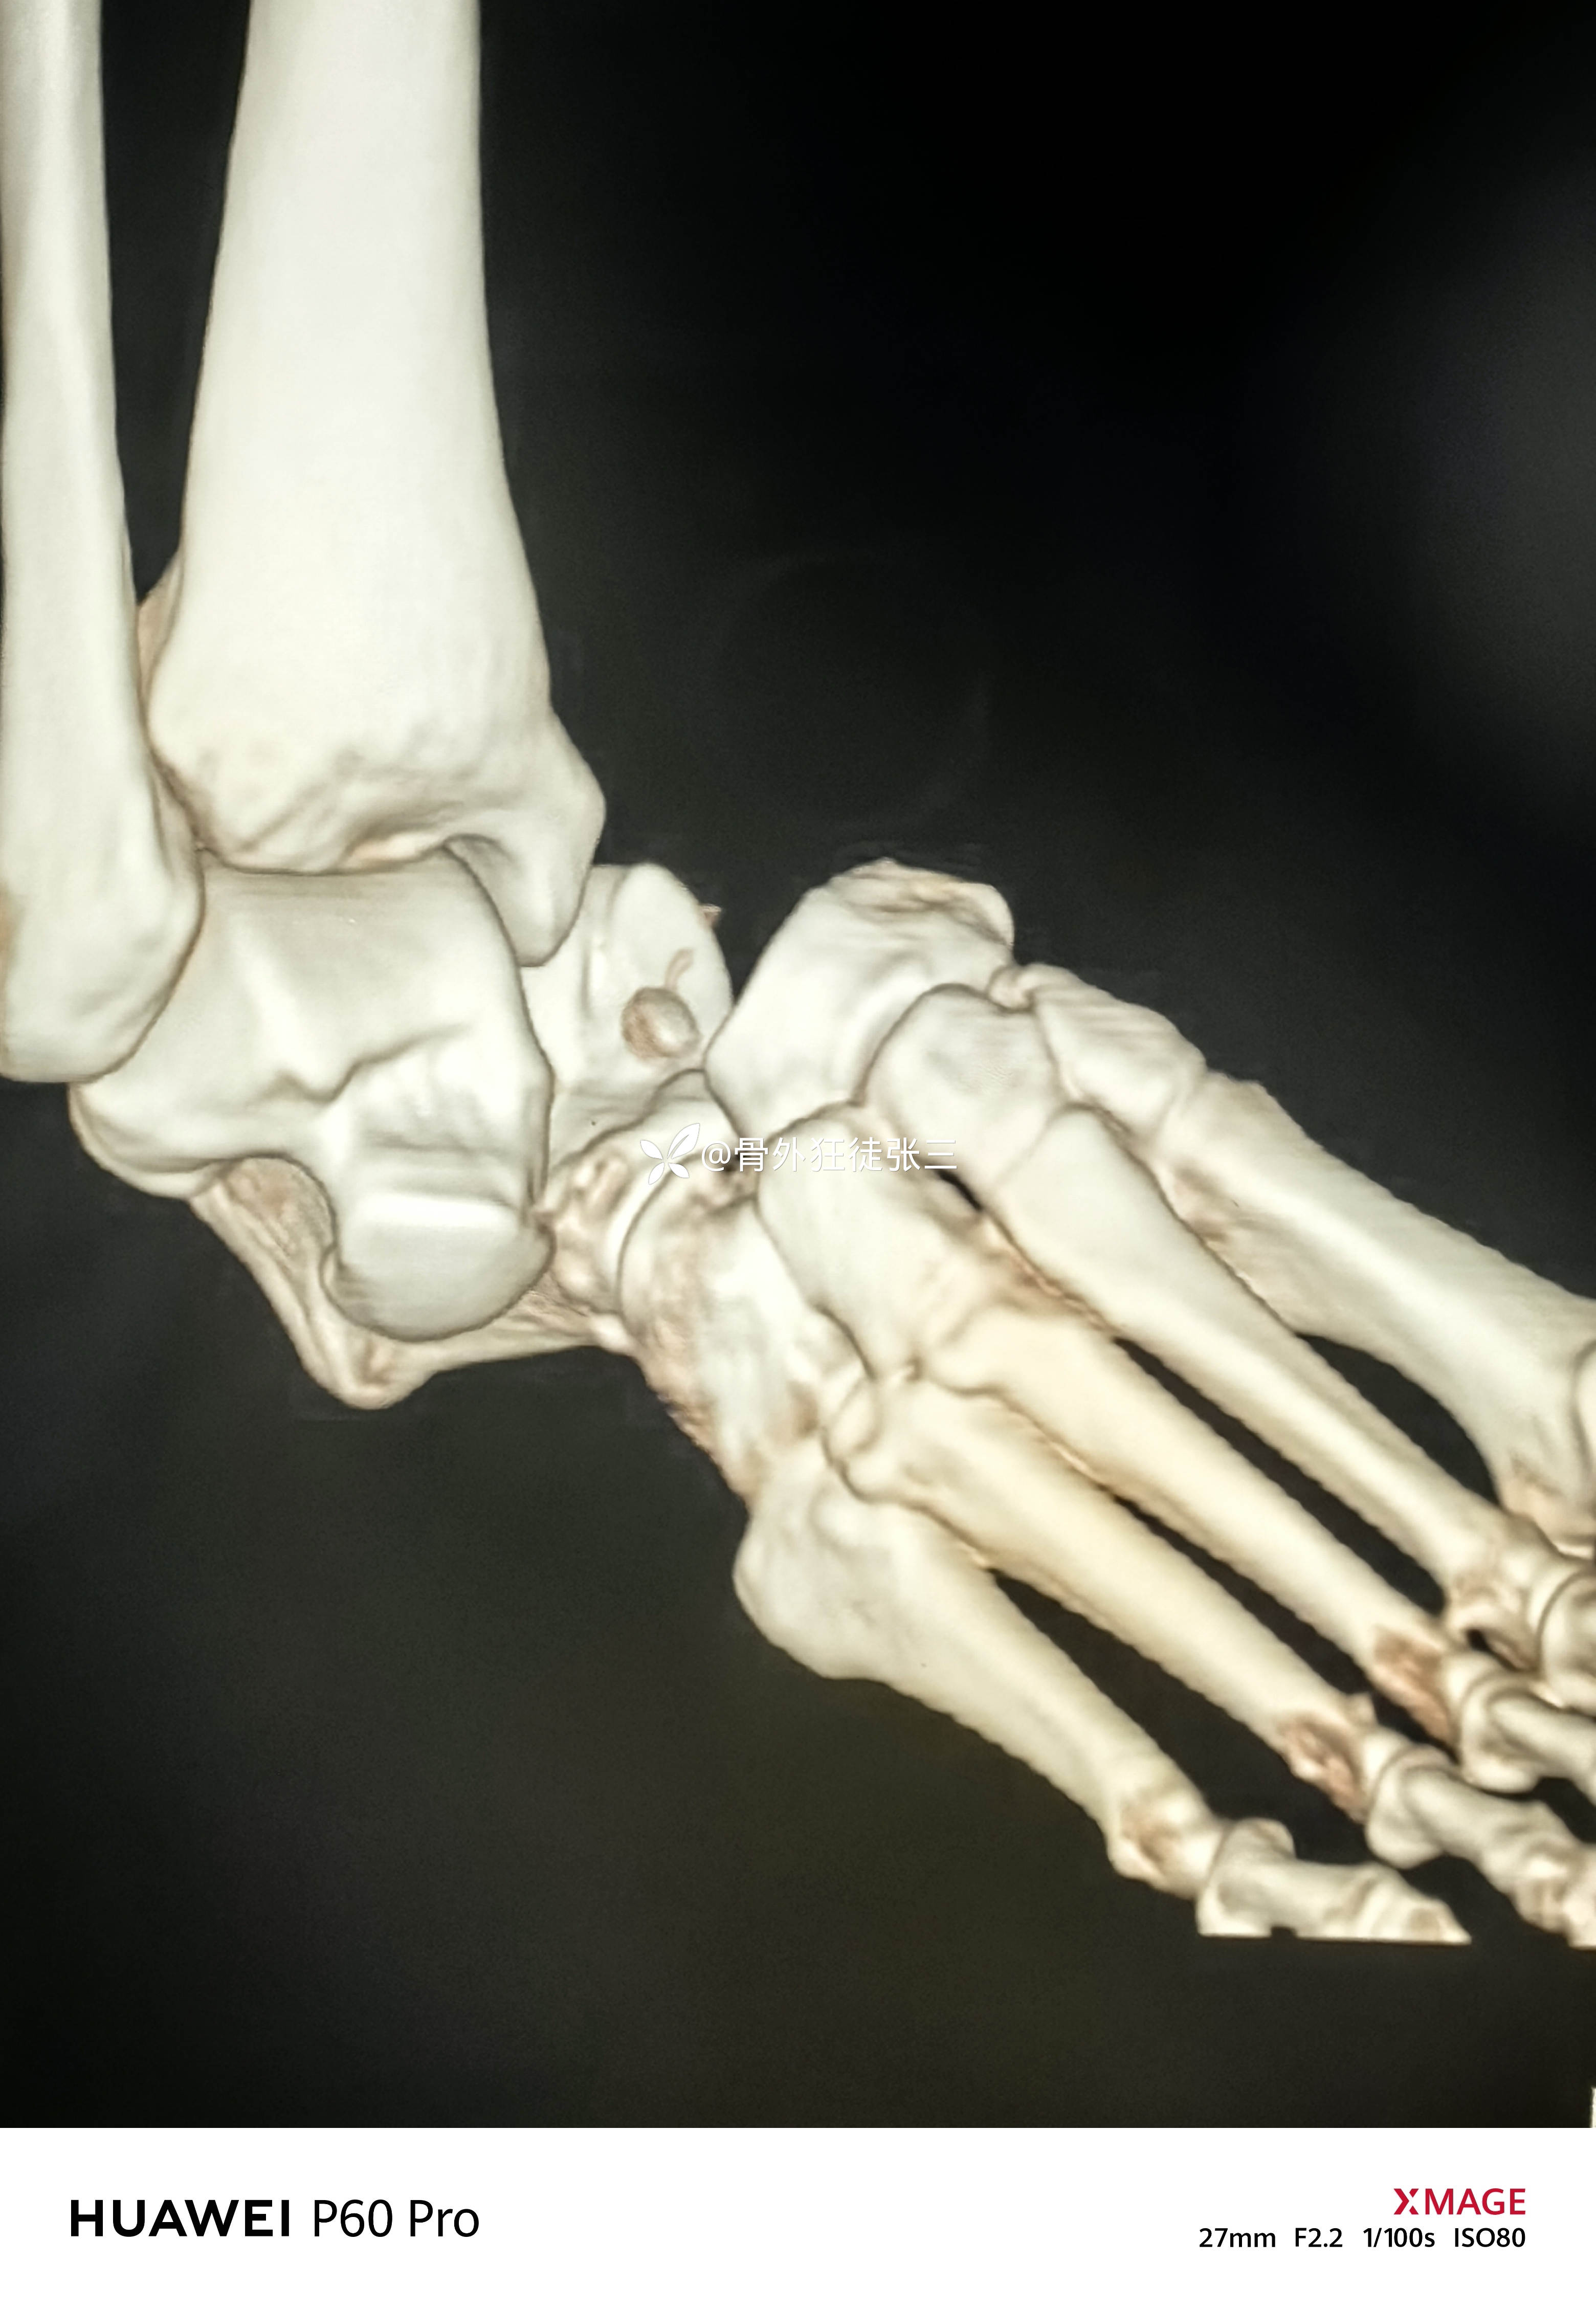

罕见损伤:距下关节脱位

右距下关节脱位(内侧型)